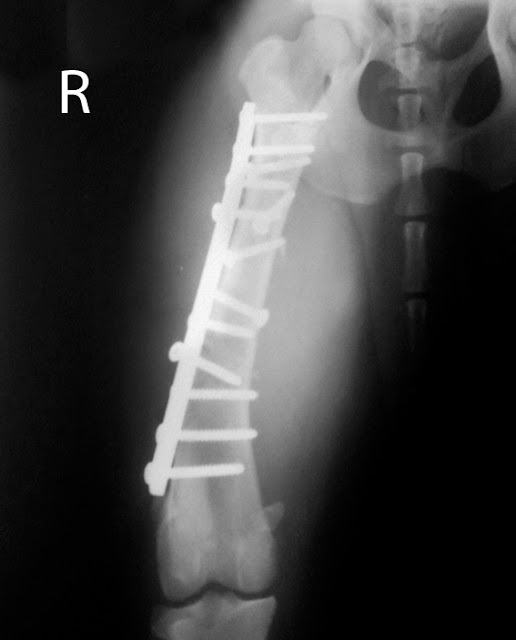

Rechazo De Placas Y Tornillos Síntomas, ES NECESARIO RETIRAR LOS TORNILLOS, CLAVOS O PLACAS DEL HUESO, 10.3 MB, 07:30, 317,110, Rafael santibañez, 2018-07-26T22:19:29.000000Z, 3, Rechazo de placas y tornillos síntomas | Actualizado noviembre 2022, larachacf.es, 1280 x 720, jpeg, WebBuenas tardes: Lo del "rechazo" muchas vecs son infecciones subagudas, es raro una reacción alérgica a metales si no hay antecedentes conocidos. Otra coas es que, por irritación mecánica local con tendones o tejidos que deslizan y se "rozan" con. WebCuando hablamos de rechazo podemos referirnos a alergia al material, infección, ausencia de fijación o pseudoartrosis, etc. Nos basamos en la sintomatología y. WebEntre los más habituales destaca la infección de la herida quirúrgica, las molestias derivadas del material implantado, la migración del material, alergia a metales, o la. Web9 señales de una herida de rechazo. Te sientes constatemente insatisfecho con lo que eres, tienes y logras. Te sientes incomprendido y considerablemente distinto., 20, rechazo-de-placas-y-tornillos-sintomas, Novedades y Muebles WebBuenas tardes: Lo del "rechazo" muchas vecs son infecciones subagudas, es raro una reacción alérgica a metales si no hay antecedentes conocidos. Otra coas es que, por irritación mecánica local con tendones o tejidos que deslizan y se "rozan" con. WebCuando hablamos de rechazo podemos referirnos a alergia al material, infección, ausencia de fijación o pseudoartrosis, etc. Nos basamos en la sintomatología y. WebEntre los más habituales destaca la infección de la herida quirúrgica, las molestias derivadas del material implantado, la migración del material, alergia a metales, o la. Web9 señales de una herida de rechazo. Te sientes constatemente insatisfecho con lo que eres, tienes y logras. Te sientes incomprendido y considerablemente distinto.

WebCuando el cuerpo no responde correctamente ante la aplicación de material de osteosíntesis posterior a intervención quirúrgica se pueden presentar síntomas como: 1.. WebSi retiras unas placas de un cúbito y radio. 6 tornillos en cada hueso. 12 agujeros debilitando esos huesos. (Es por ahí que en caso de caída se vuelve a. WebEl sitio quirúrgico de una fractura de tobillo es una zona superficial y altamente inervada que puede conllevar molestias como piquetes, punzadas o sensación de roce. WebHola Enrique. Las nuevas placas bloqueadas tienen sistemas de rosca entre el tornillo y la placa, por lo que no es habitual que se desmonten. Sin embargo, sí que es cierto que. WebLa osteosíntesis es una cirugía cuyo objetivo es unir los fragmentos óseos. Los dispositivos que se utilizan en esta cirugía son diversos, como placas, tornillos, clavos,. WebLos tornillos y las placas que se establecen demasiado firmemente contra el hueso pueden resultar en estrés blindaje, en el que el metal tiene demasiada carga de. Webretiro de tornillos fractura dr rafael santibañez ortopedia informacion general WebLa infección puede manifestarse principalmente con síntomas de dolor, absceso intraoral, inflamación de la zona, exposición de la placa y sinusitis en caso de.

WebBuenas noches doctor hace 3 meses me operaron de la meseta tibial, me pusieron 2 placas y 12 tornillos, lo cual no me cicatriza la herida y una parte del metal esta. WebSíntomas. Si tienes un tobillo quebrado, es posible que presentes algunos de los siguientes signos y síntomas: Dolor inmediato y pulsátil; Hinchazón; Hematomas;. WebSi el problema se relaciona con tornillos o placas que se rompen, o de características inapropiadas (p. ej.: estrechas, cortas, etc.), es necesario replantear la.